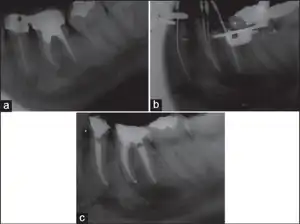

Dentistry

Paresthesia or "persistent anesthesia" is a transient or potentially permanent condition of extended numbness after administration of local anesthesia and the injected anesthetic has terminated.[15]

Potential causes include trauma introduced to the nerve sheath during administration of the injection, hemorrhage about the sheath, type of anesthetic used, or administration of anesthetic potentially contaminated with alcohol or sterilizing solutions.[16]